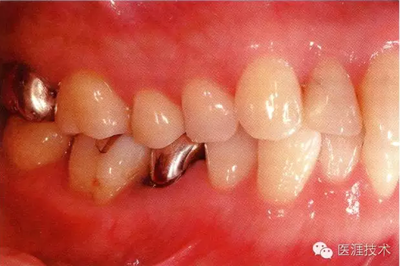

28歲女性的健康口腔內(nèi)部

圖為28歲女性,無特殊全身疾病,不抽煙。10年前來院就診保養(yǎng)3年,期間中斷過,現(xiàn)又開始。齲壞風險高,當初初診時已有好幾顆牙的鄰面有填充物,再填充了3牙的鄰面齲,現(xiàn)牙周組織健康。